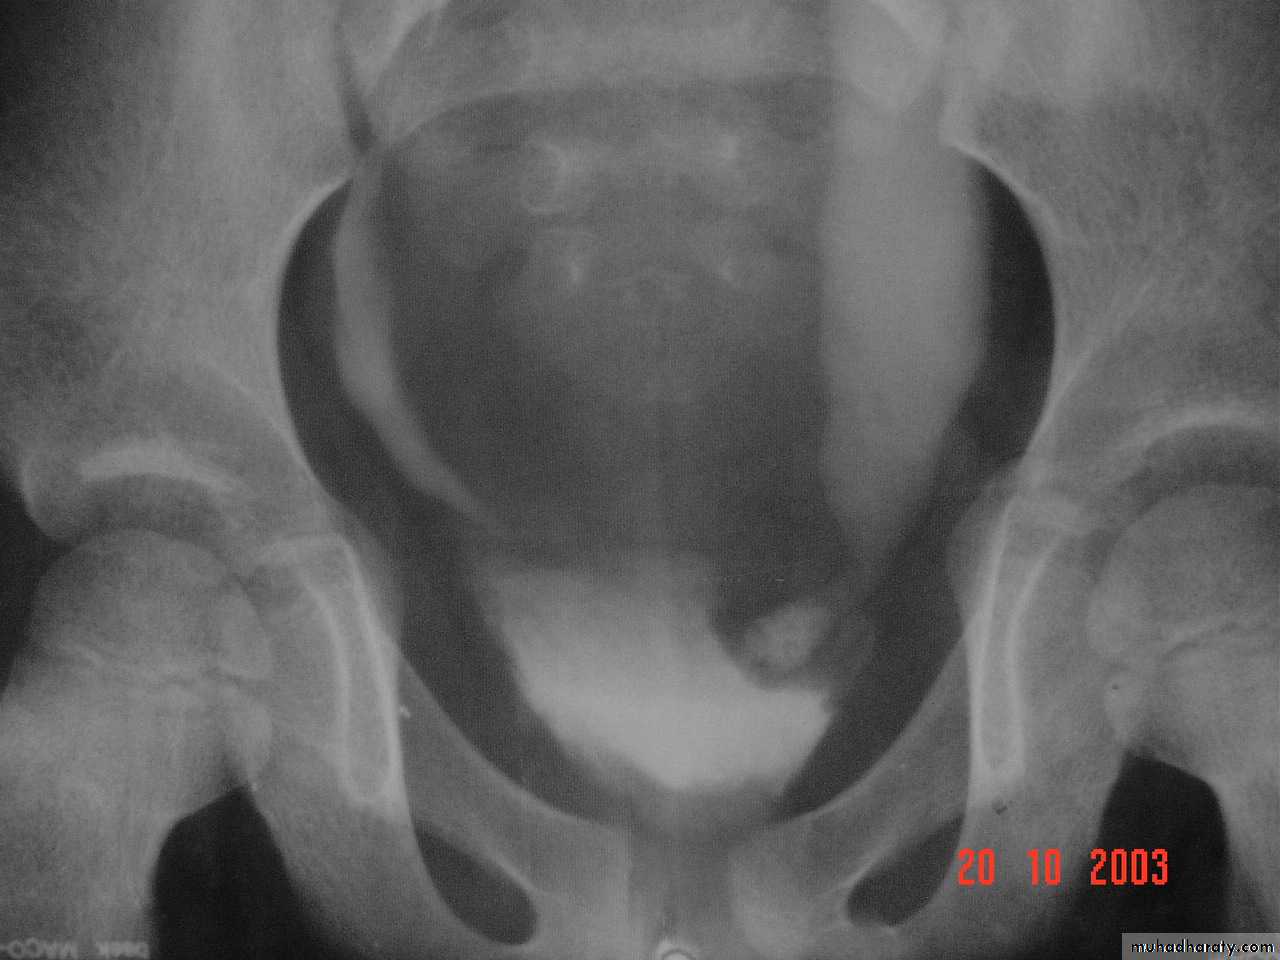

:*Ectopia vesica :-bladder located at low position with separartion of symphysis pubis.